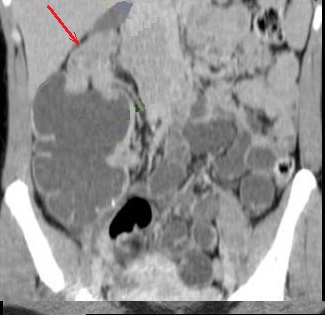

Adenocarcinome du caecum :

Mass hyper-dense en bourgeonante non

homogene du caecum ( fleche rouge ) . Image

radiologique TDM en coupe coronale . |